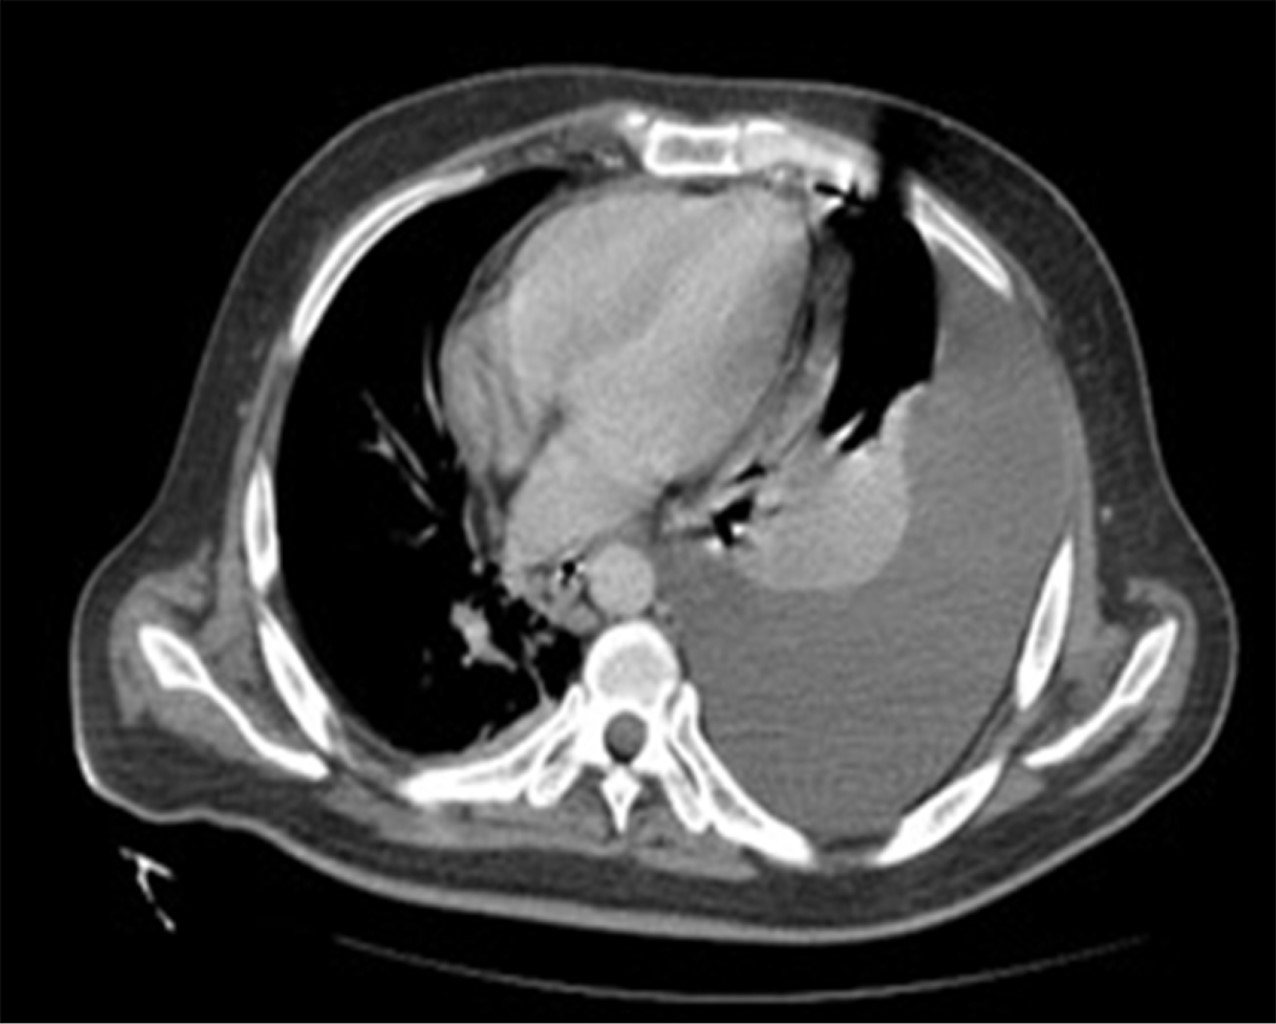

Se realizó una radiografía anteroposterior (AP) de tórax, en la cual se visualizó un derrame pleural izquierdo que cubría más de 50%. La tomografía computarizada mostró una importante cantidad de líquido en el espacio pleural izquierdo que condicionó una atelectasia pasiva del lóbulo inferior (Figura 1); el hígado se encontró con densidad heterogénea con incremento del lóbulo hepático izquierdo secundario a la presencia de una lesión heterogénea hipodensa con bordes lobulados, que muestra un reforzamiento periférico y de algunos septos internos, la cual abarca los segmentos II, III, IVa y IVb midiendo aproximadamente 20 × 14.5 × 12.5 cm (Figura 2), condicionando desplazamiento posterior y compresión del estómago y del páncreas y desplazamiento caudal de las asas intestinales (Figuras 3 y 4). En el polo inferior del lóbulo hepático derecho adyacente al segmento IV se identifica una lesión de aspecto quístico homogéneo con reforzamiento periférico tras la administración de contraste intravenoso, midiendo en sus ejes mayores 25 × 27 × 13 cm. Como manejo inicial se le colocó una sonda Foley y sonda nasogástrica presentando gasto de características gástricas (30 ml). Se colocó un catéter central, verificado por radiografía. Se solicitaron estudios de imagen. Se le indicó ayuno, se inició fluidoterapia, antibioticoterapia con ceftriaxona y metronidazol, manejo del dolor, control glucémico y protector gástrico. Al visualizar la imagen del derrame pleural izquierdo, se decide realizar una toracocentesis, obteniendo exudado espeso de aspecto "chocolatoso". Al momento de contar con la tomografía se inicia tratamiento quirúrgico urgente.

Figura 4